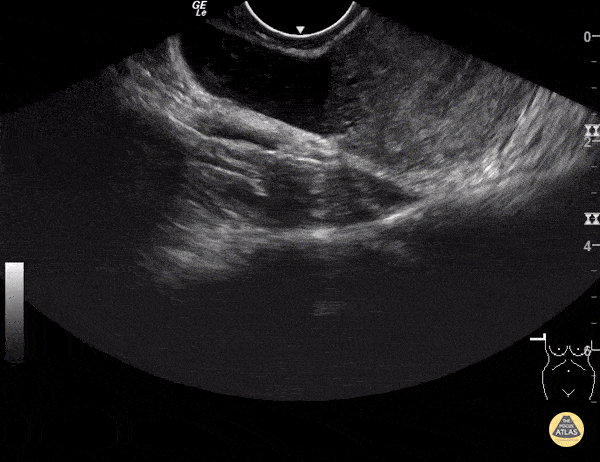

https://www.thepocusatlas.com/obgyn